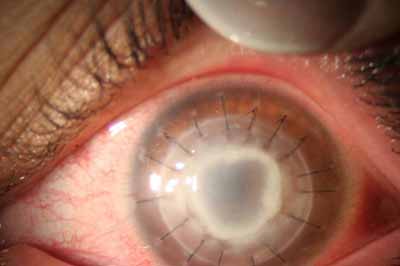

- Recubrimiento Conjuntival en inminencia de perforación

- Para Injerto de córnea si precisa, esperar 1 año o mas después de la curación

Cuando la invasión por Acanthamoebas es estromal, la respuesta celular tiene como consecuencia, que la abscesificación del estroma continuará aumentando a pesar del tratamiento….. y su resolución es lenta.